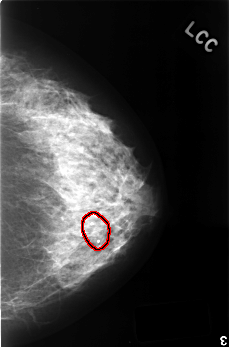

FILE: C_0407_1.LEFT_CC.OVERLAY

TOTAL_ABNORMALITIES 1

ABNORMALITY 1

LESION_TYPE CALCIFICATION TYPE DYSTROPHIC DISTRIBUTION SEGMENTAL

ASSESSMENT 2

SUBTLETY 5

PATHOLOGY BENIGN_WITHOUT_CALLBACK

TOTAL_OUTLINES 1

BOUNDARY